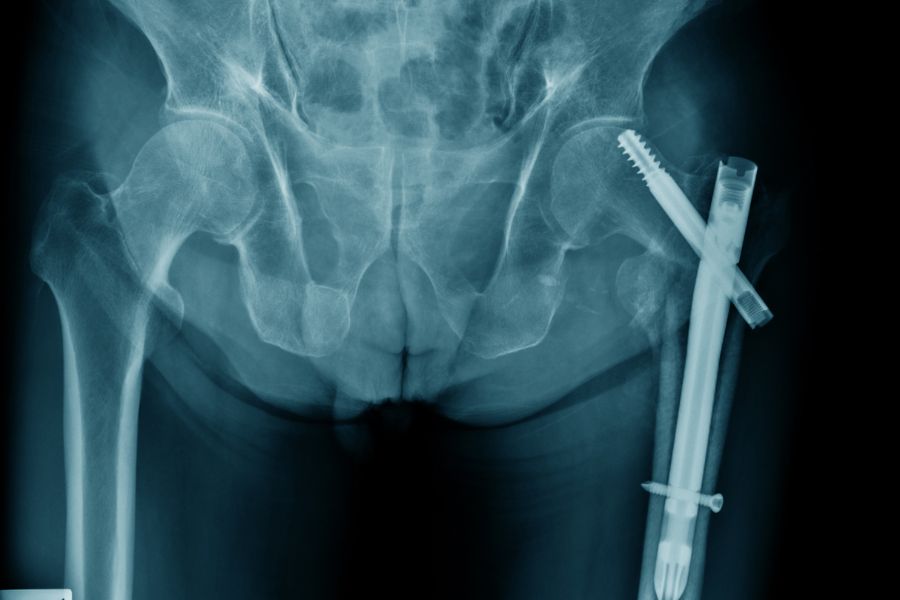

• Kırık: Protez çevresindeki kemikte oluşan kırıklar.

Revizyon kalça protezi cerrahisi, ilk ameliyata kıyasla daha ileri düzey planlama ve deneyim gerektirir. Tedavi planı hastanın kemik durumu, enfeksiyon varlığı ve protez tipine göre belirlenir.

3. Kemik Grefti ve Özel Protezler

Kemik kaybı fazlaysa, greft (kemik tozu veya yapay kemik) kullanılarak yapı desteklenir. Gelişmiş özel dizayn protezlerle eklem yeniden şekillendirilir.